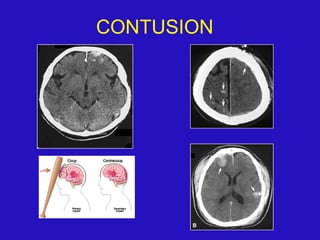

CONTUSION:-

 Common type of primary intra-axial lesion .

In 21% of head trauma patients.

 PATH :- Tissue necrosis, capillary disruption,

petechial hemorrhage followed by

liquefaction + oedema after 4 to 7 days

.contusion may be hemorrhagic or non-

hemorrhagic.

 MECHANISM :- Linear acceleration –

deceleration forces / penetrating trauma /

direct impaction.

1. COUP :- Direct impact to stationary brain. Injury at

the site of impaction.

2. COUNTER COUP :- Impact of moving brain on

stationary clavarium opposite to the site of the coup

and produced injury.

 Contusions are typically superficial foci of punctate

or linear hemorrhages that occur

along gyral crests.

 Location - Multiple bilateral lesion , temporal lobes

most frequently involved.

- Bneath an acute subdural hematoma.

 C.T

- Initial findings may be subtle or absent.

- Early findings focal / multiple poorly defined

areas of low attenuation with irregular contour

intermixed with a few tiny areas of increased

density ( petechial hemorrhage)

- Diffuse oedema and mass effect in immediate

post-traumatic period,then gradually diminish

over time.

- Some degree of contrast enhancement.

- Isodense to brain after 2 – 3 weeks.